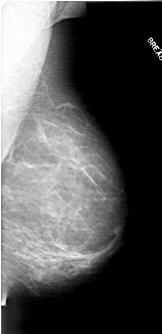

A_1711_1.LEFT_CC

LEFT_CC LINES 6001 PIXELS_PER_LINE 3091 BITS_PER_PIXEL 12 RESOLUTION 43.5 OVERLAY